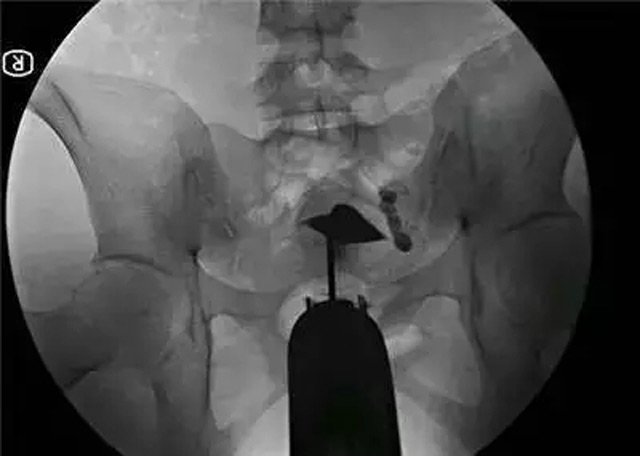

目前对输卵管堵塞部位、程度最准确的检查方法,仍是输卵管造影,一般在月经完结后的第三天至第七天做检查。输卵管堵塞的部位不同,手术治疗方法也不同。